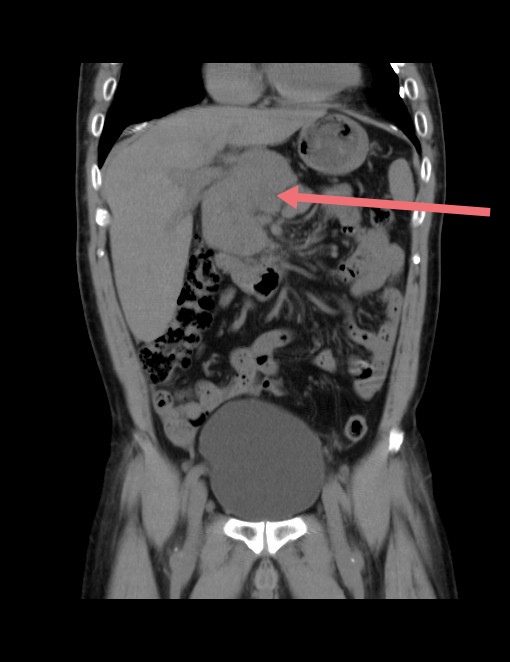

腹腔深部包块CT冠状位图像

腹腔霍奇金淋巴瘤CT冠状位图像